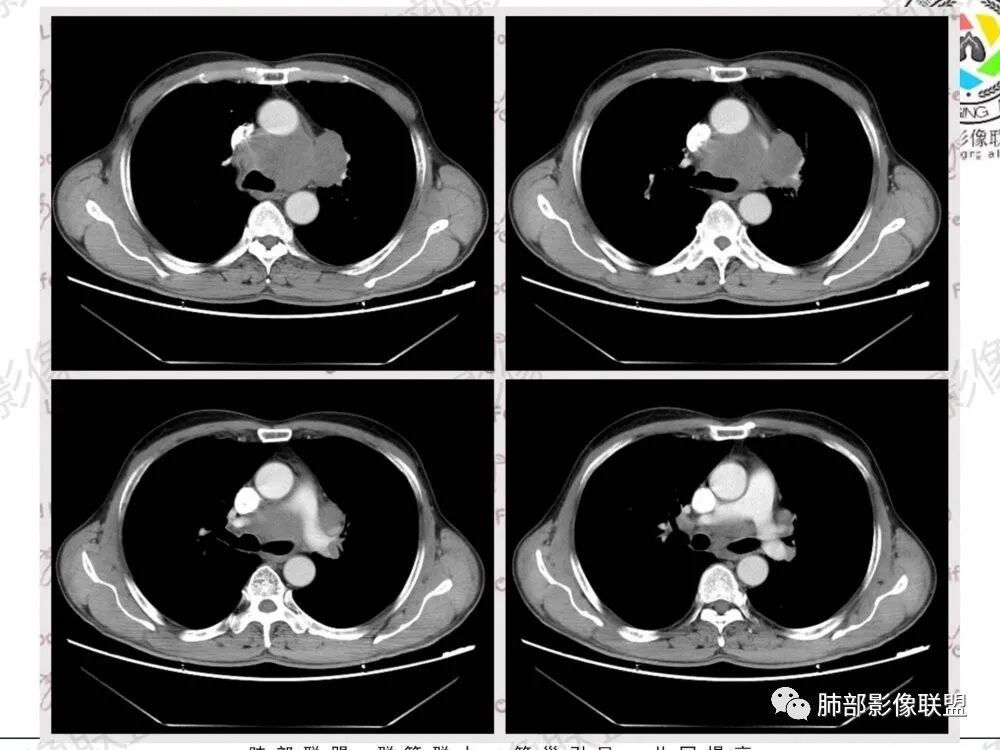

57岁男性,长期吸烟史,有血吸虫病史,有粉尘接触史。发现纵隔淋巴结肿大2年,声嘶伴咳嗽咳痰半月。两年前胸部CT见左上肺尖后段结节并肺门淋巴结肿大,治疗后左上肺结节消失。目前胸部CT:肺气肿,左上肺尖后段见条索影(原来结节治疗后的改变?),肺门、纵隔淋巴结肿大并融合,似见薄壁包膜样强化。考虑淋巴结结核可能性大,注意鉴别淋巴瘤、转移、结节病等。

纵隔多发肿大淋巴结,明显融合,增强扫描有边缘环形线样强化,考虑结核,其次转移,血吸虫没见过。平日工作中遇上还是建议穿刺活检了

病史两年,左肺病变治疗后有吸收,需要结合老片对比,有血吸虫,粉尘史,纵隔及肺门淋巴结肿大,淋巴结形态消失,部分融合,周围血管挤压,增强后环形强化,肺内可见多发肺气肿,左肺尖可见纤维索条影(可能既往有陈旧性结核),综合考虑:一元论:结核(纵隔淋巴结及左肺都是结核),二元论:肿瘤性病变合并左肺结核(纵隔淋巴瘤,如果是小细胞肺癌的这么大淋巴结,肺内病灶没有转移,有点奇怪)

纵膈及左肺门多发肿大淋巴结,部分融合呈团块状,密度不均,增强后轻度边缘强化,考虑转移,鉴别淋巴结结核

位移:

纵隔及左肺门多发肿大淋巴结,融合团块状,密度不均,增强后轻度边缘强化,中央似有坏死,考虑转移瘤,鉴别淋巴瘤

中老年男性,长期吸烟,肺气肿明显,发现纵隔淋巴结两年了,声音嘶哑,病灶压迫喉返神经了?喉部有占位吗?左肺尖小片状病灶,周围多发长条纤维牵拉,胸膜增厚,纵隔及左肺门多发肿大淋巴结,增强后显示淋巴结融合且坏死明显,薄环状强化。如果是恶性肿瘤,小细胞癌或者鳞癌,肺内病变应该增大增多了;一元化我考虑纵隔淋巴结结核,左肺尖结核灶。

1.左肺门及纵隔见异常增大淋巴结,部分融合,不均匀轻度强化,未见明显坏死。

肿大淋巴结与纵隔血管等结构“无缝”贴合。

2.纵隔增宽但依旧居中。

1.这应当是常见的小细胞肺癌的转移方式。

别忘了,患者左肺上叶那个略显饱满的的小结节,有理由相信那是发源地。

2、小细胞癌恶性程度高,发展迅速,转移发生早;常有纵隔淋巴结的明显增大融合(发生率达96.5%),呈“冰冻纵隔”,淋巴转移常为逐站的连续性转移;亦有血行转移,脑、肾上腺、肝、胰、骨髓等;转移灶常比原发灶大得多,即“娘小崽大”特点;